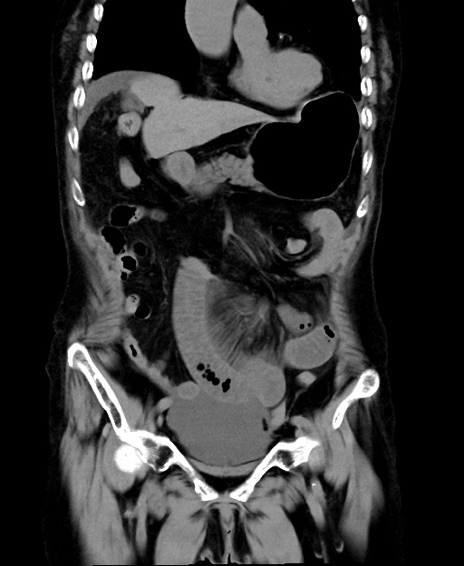

冠状断像

他院CT